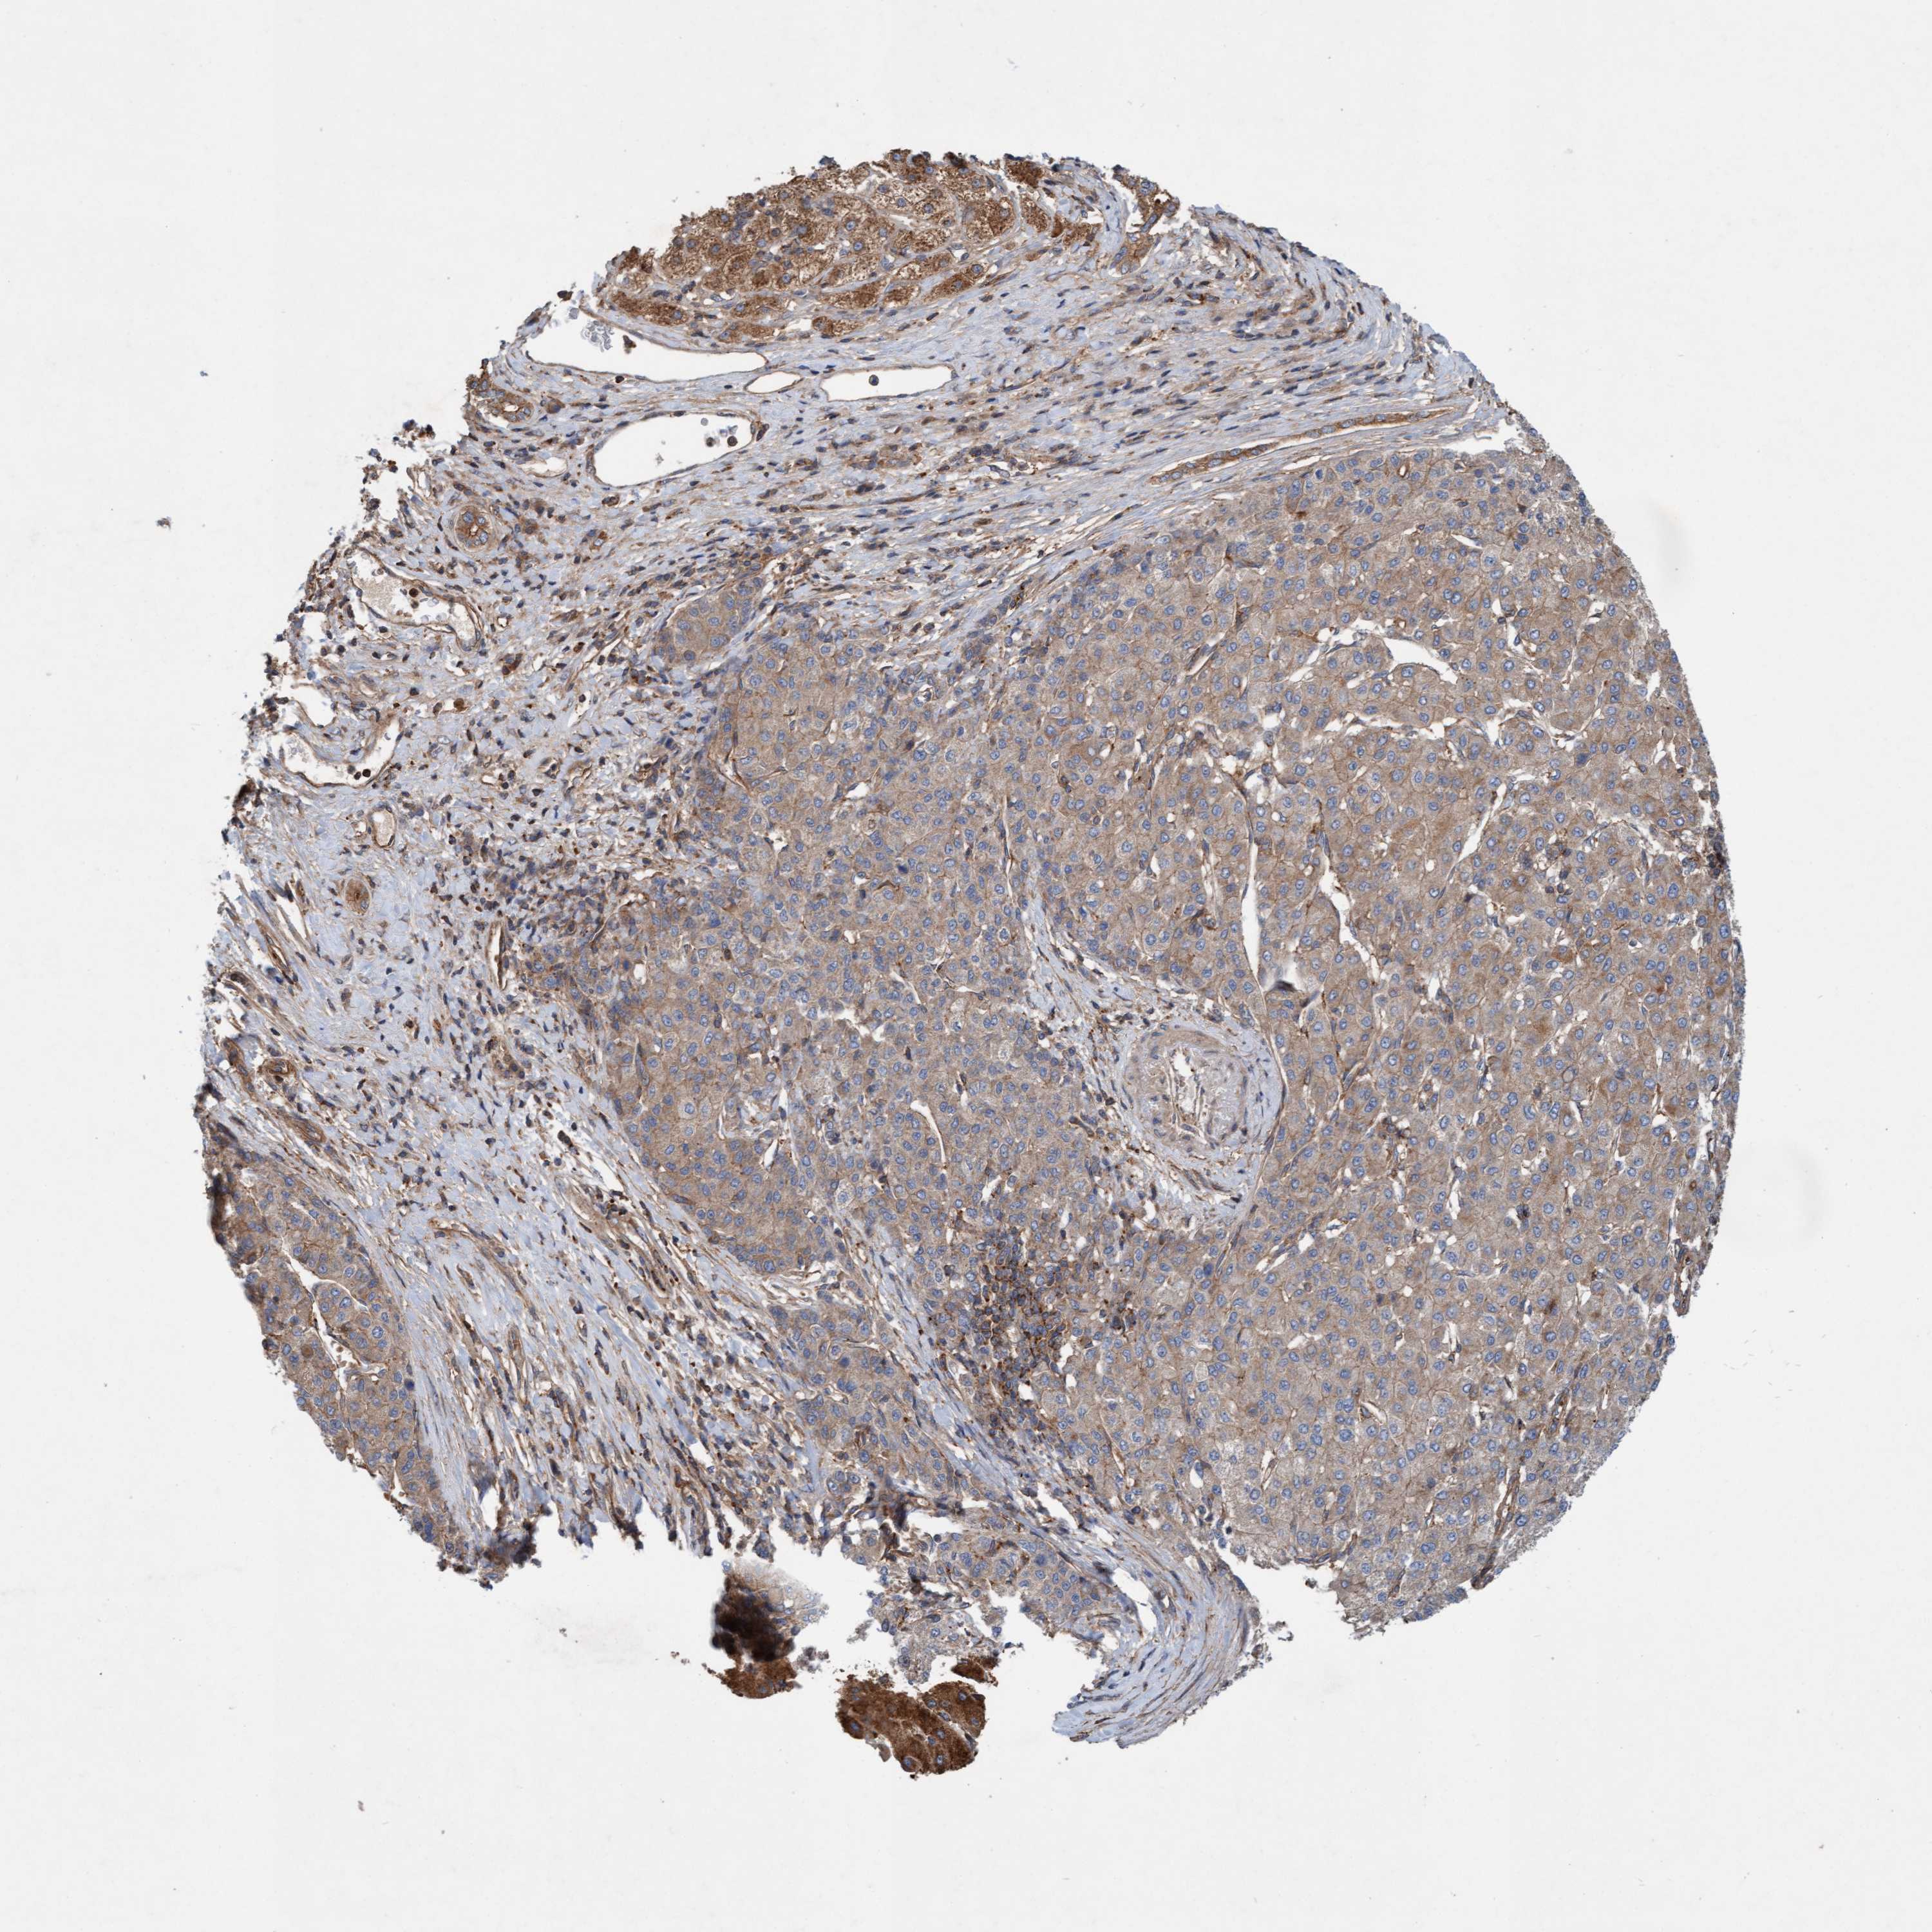

LIVER CANCER - Protein expressioni

A mouse-over function shows sample information and annotation data. Click on an image to view it in a full screen mode. Samples can be filtered based on level of antibody staining by selecting one or several of the following categories: high, medium, low and not detected. The assay and annotation is described here.

Note that samples used for immunohistochemistry by the Human Protein Atlas do not correspond to samples in the TCGA dataset.

Antibody stainingi

Antibody staining in the annotated cell types in the current human tissue is reported as not detected, low, medium, or high, based on conventional immunohistochemistry profiling in selected tissues. This score is based on the combination of the staining intensity and fraction of stained cells.

Each image is clickable and will lead to virtual microscopy that enables deeper exploration of all samples and also displays staining intensity scores, fraction scores and subcellular localization as well as patient and tissue information for each sample.

Antibody HPA021425

Antibody HPA024423

Staining

High

Medium

Low

Not detected

Intensity

Strong

Moderate

Weak

Negative

Quantity

>75%

75%-25%

<25%

None

Location

Nuclear

Cytoplasmic/membranous

Cytoplasmic/membranous,nuclear

Cholangiocarcinoma

Carcinoma, Hepatocellular, NOS